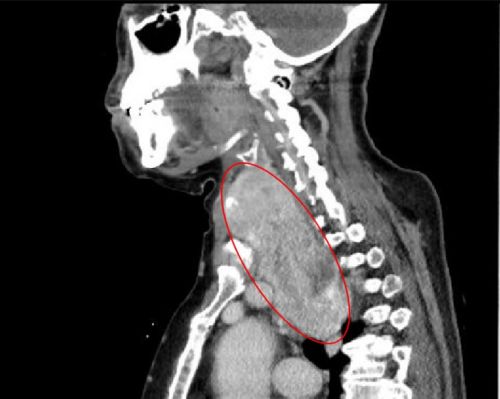

ct显示:巨大的右侧甲状腺肿瘤从颈部延伸至胸腔。